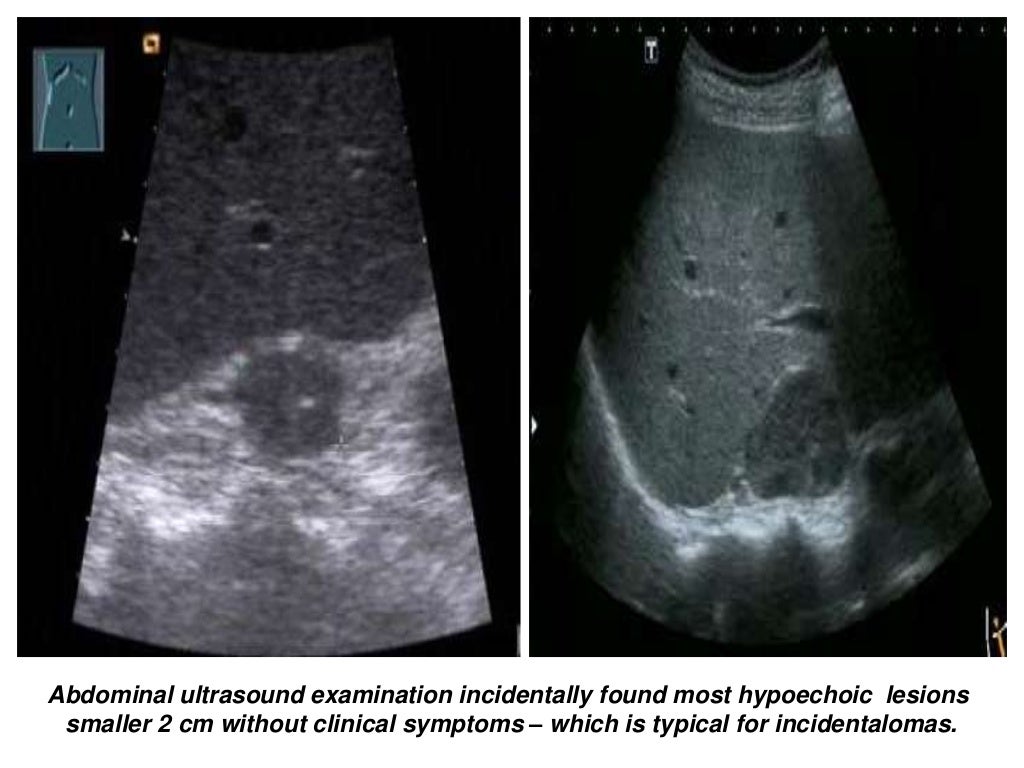

Abdominal ultrasound Adrenal Gland Ultrasound Preparation Perform a real time survey of the adrenal glands. Any lesion growth is suspicious for malignant disease (fig. adrenal glands ultrasound patient prep: the left adrenal gland is imaged by a posterolateral approach in coronal plane through the long axis of the. Scan technique, patient positioning and anatomic consideration for adrenal sonography. adrenal gland visualization in a. Adrenal Gland Ultrasound Preparation.